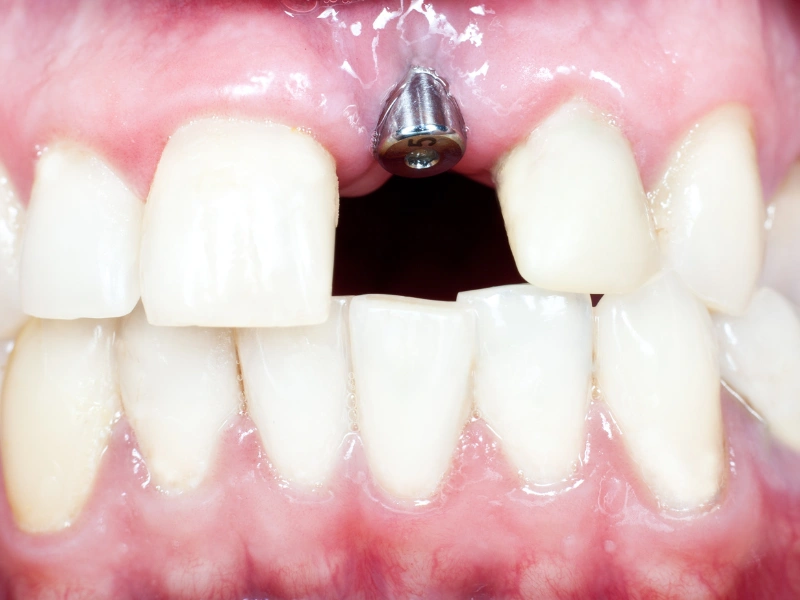

Atención integral en salud oral para toda la familia: desde controles de rutina hasta tratamientos de rehabilitación, estética y ortodoncia, en un mismo lugar.

Odontología integral Diagnóstico digital y preciso Enfoque preventivo y estético

Cuidamos tu salud oral en cada etapa

Especialidades dentales